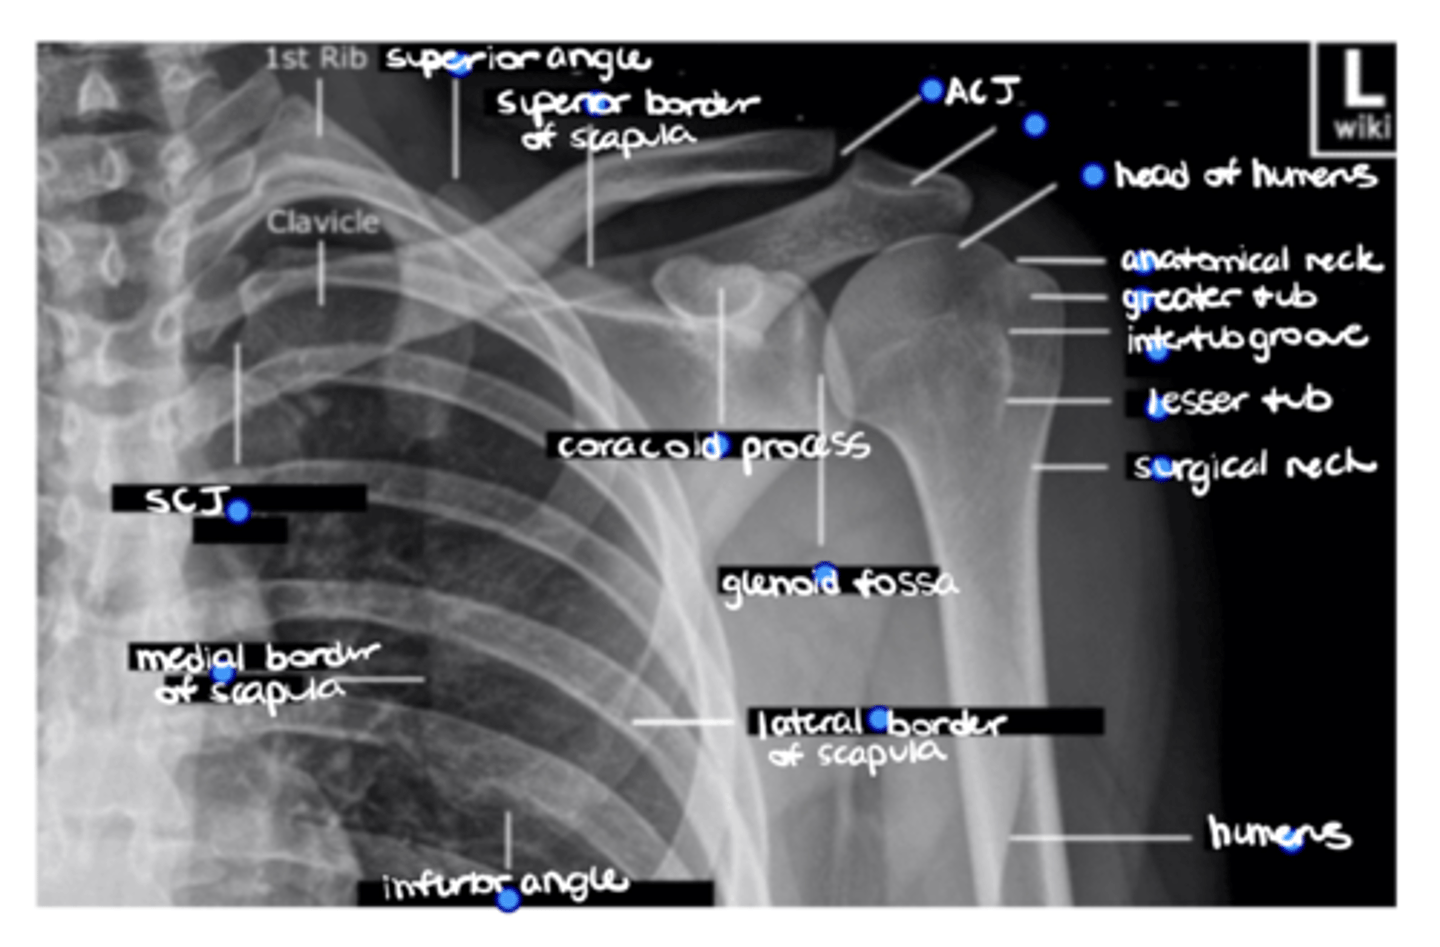

Superior angle of the scapula

ID the missing structure.

Superior border of the scapula

ACJ

Acromion

1. Head of humerus

2. Anatomical neck

3. Greater tuberosity

4. Intertubercular groove

5. Lesser tuberosity

6. Surgical neck

ID the 6 missing structures.

Shaft of the humerus

1. Coracoid process

2. Glenoid fossa

ID the 2 missing structures.

1. Lateral border of the scapula

2. Inferior angle of the scapula

3. Medial border of the scapula

ID the 3 missing structures.

SCJ